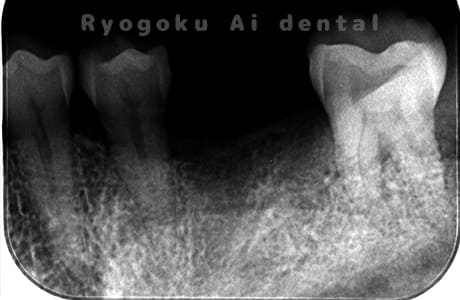

Case07

- 原因

- 右下6番歯根破折

-

- 治療内容

- インプラント治療

- 治療費用

- 約600,000円

右下の腫れが治らないとの事でご来院された患者様です。歯が割れていたため、抜歯を行い、骨に代わるお薬を入れ、インプラントを埋入致しました。経過良好で大変満足していただけました。

<リスク・副作用>

治療後、痛みや違和感、出血、腫れなどが出る事があります。喫煙者、糖尿病などの方の場合、歯が生着しない場合があります。